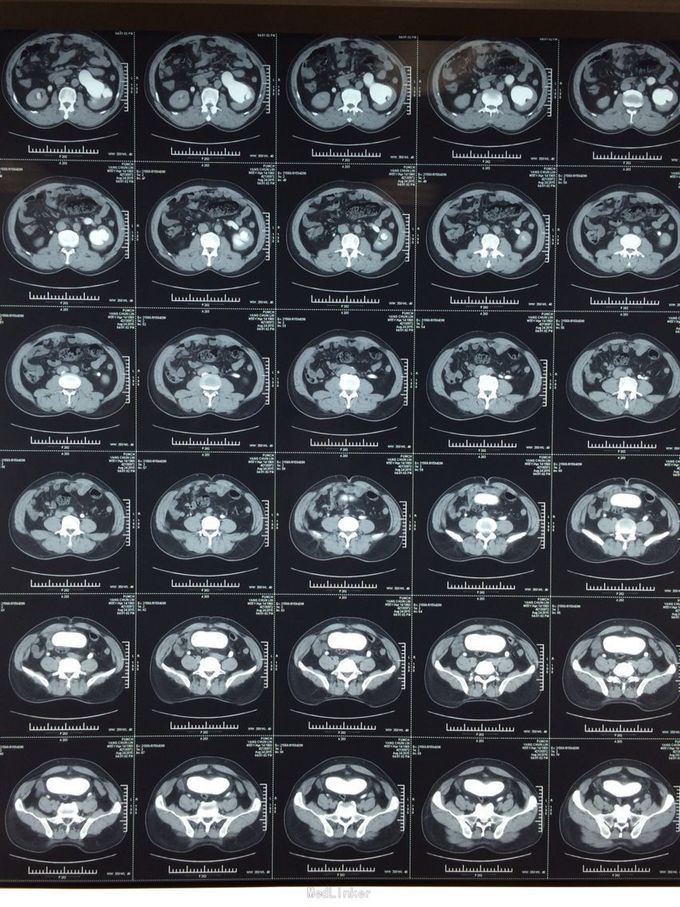

体检发现左肾积水3月余。无尿频尿急,排尿困难。当地医院彩超示:1双肾积水2右输尿管扩张3左侧输尿管走形迂曲并扩张4膀胱位置抬高5前列腺显示不清。为求进一步治疗前来我院。门诊行检查后诊断为盆腔脂肪增多症,建议患者行左肾造瘘。患者表示拒绝,至北京某医院就诊,给予行双侧输尿管D-j管置入,未成功。再次至我院就诊,门诊以“盆腔脂肪增多症”收住院。

盆腔脂肪增多症诊断目前没有统一标准,目前比较公认的是:CT,MRI发现盆腔脂肪异常增多;膀胱受压变形呈梨形、泪滴状或香蕉状;腺性膀胱炎表现;直肠-乙状结肠明显受压拉直,结肠袋消失;合并肾积水. 满足以上1或+ 2-5任意一条即可诊断;个人认为MRI提供的参考信息大于CT。输尿管D-J置入往往因输尿管受压迂曲而失败,无法缓解病情。输尿管皮肤造瘘或肾造瘘也许是这些患者的最终结局,高位的回肠代膀胱也是一种选择但存在肾积水缓解不好的风险。需要特别指出盆腔脂肪剃除不可取。长期来看输尿管膀胱再植也是无效的。